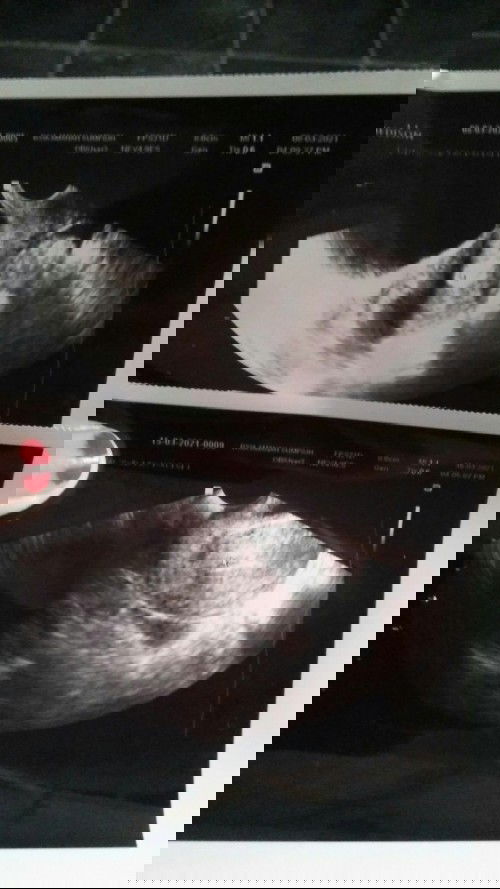

Yang atas hasil usg pertama setelah flek menyerupai menstruasi. Yg kedua hasil usg evaluasi selama seminggu setelah saran dari dokter. Kata dokter bisa jadi sudah keguguran. Karena sudah tidak terlibat tanda2 adanya janin atau kantong rahim. Padahal usia kehamilan saya waktu itu 7 mnggu lewat 4 hari. Akan tetapi dokter mengatakan saya tdk perlu dikiret/ kuret . Semangat buat bunda yg mengalami seperti saya.